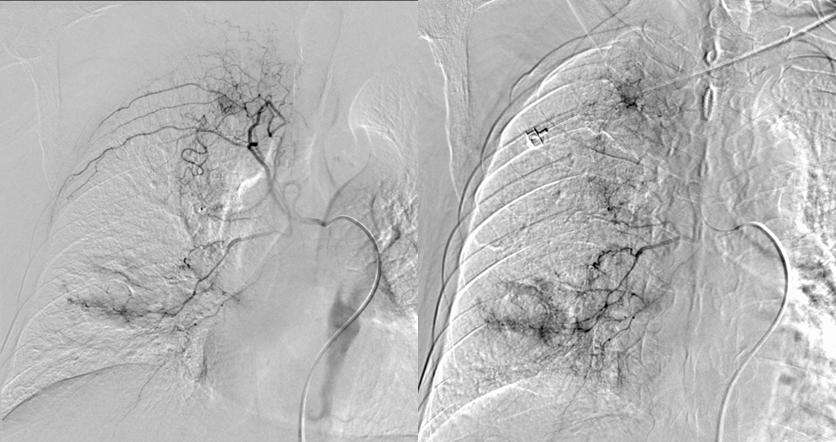

介入手术治疗(2020.7.31)

*支气管动脉造影:右侧支气管动脉与右侧最上肋间动脉共干。

*支气管动脉造影:右下肺癌性空洞壁形成。

*栓塞治疗:奥沙利铂100mg灌注化疗后300-500μm微球1瓶搭载吉西他滨1000mg进行适量栓塞, 栓塞后复查肿瘤染色大部分消失。